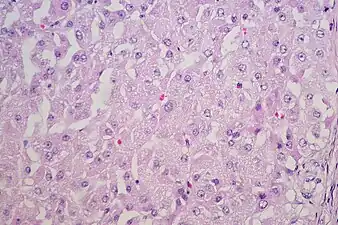

Luteoma-of-pregnancy -

Lutel cells with round uniform nuclei with visible nucleoli